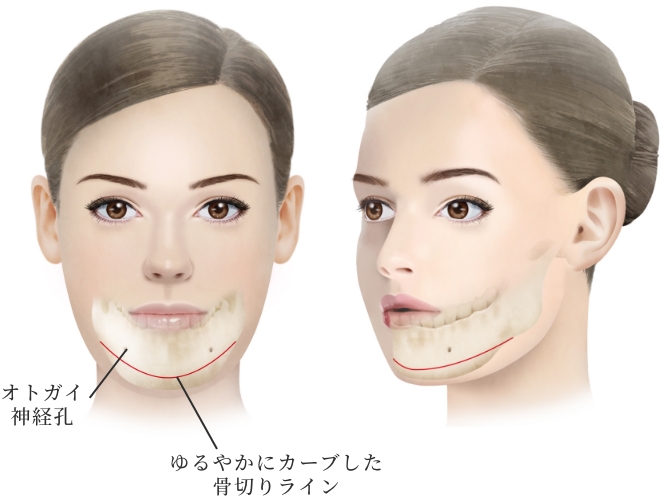

小木曽クリニックの

『オトガイ形成骨切り術』の

特徴

骨切り量が非常に大きい

オトガイ神経を剥離して下顎骨を広範囲に露出し、神経の上下からアプローチするため、骨切り範囲がオトガイ部先端から下顎角直前におよび、切除幅8㎝~10㎝、全長14cm~16cmと非常に大きい。

スムーズなカーブラインの

骨切りが可能

骨切りカッターを垂直に骨に当てるため、下顎角直前までスムーズなカーブラインの骨切りが可能。

希望に応じた

Vラインのオトガイ形成

オトガイ部先端から下顎角直前までの広い範囲の骨切りによってシャープなVライン形成が可能。